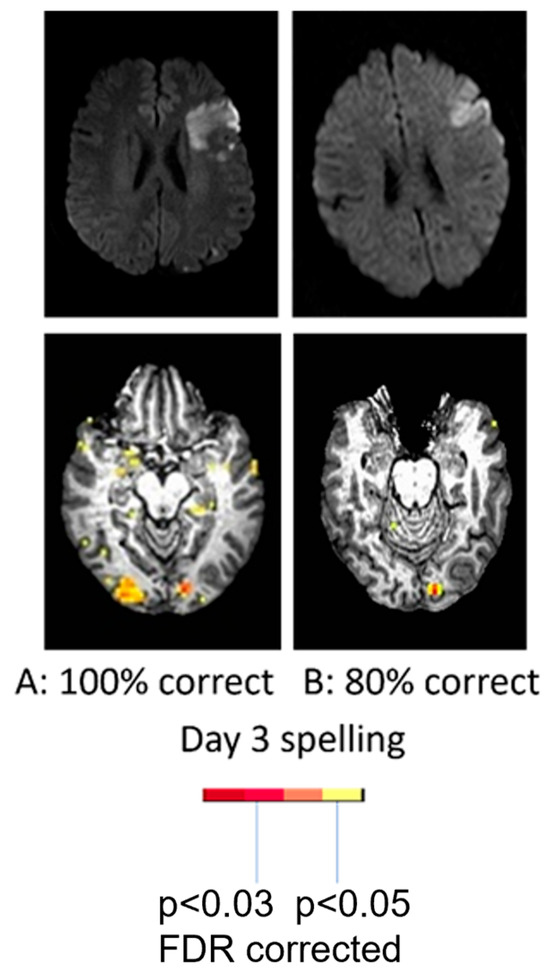

- Purcell, J.; Sebastian, R.; Leigh, R.; Jarso, S.; Davis, C.; Posner, J.; Wright, A.; Hillis, A.E. Recovery of Orthographic Processing after Stroke: A Longitudinal FMRI Study. Cortex 2017, 92, 103–118. [Google Scholar] [CrossRef] [PubMed]